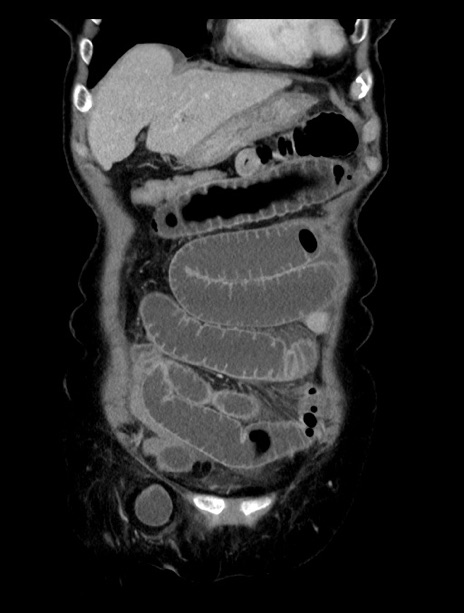

症例23(冠状断像)

【症例】70歳代女性

【主訴】下腹部痛・嘔吐

【現病歴】2日前より腹痛あり。昨日嘔吐あり。症状改善しないため来院。

【既往歴】胃GISTに対して胃部分切除後。

【身体所見】BT 37.1℃、BP 128/77mmHg、腹部:平坦・軟、下腹部に圧痛あり。

【データ】WBC 10200、CRP 0.31